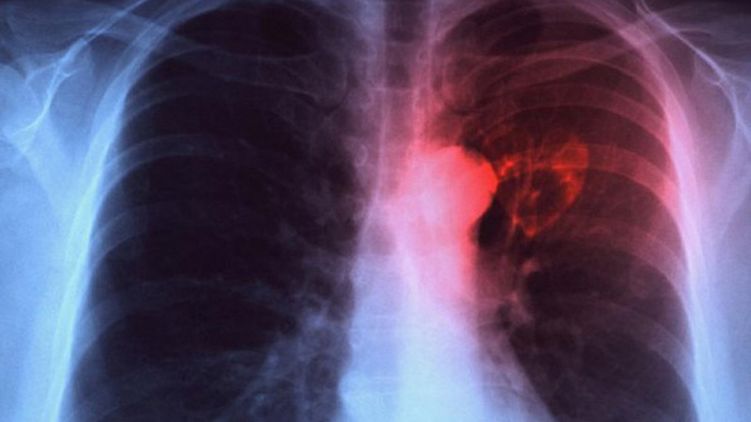

Минздрав предрек Украине вспышку туберкулеза

Если сложная ситуация с финансированием медучереждений не изменится в ближайшее время в Украине случится вспышка туберкулеза. Дефицит бюджета противотуберкулезных больниц доходит до 80%.